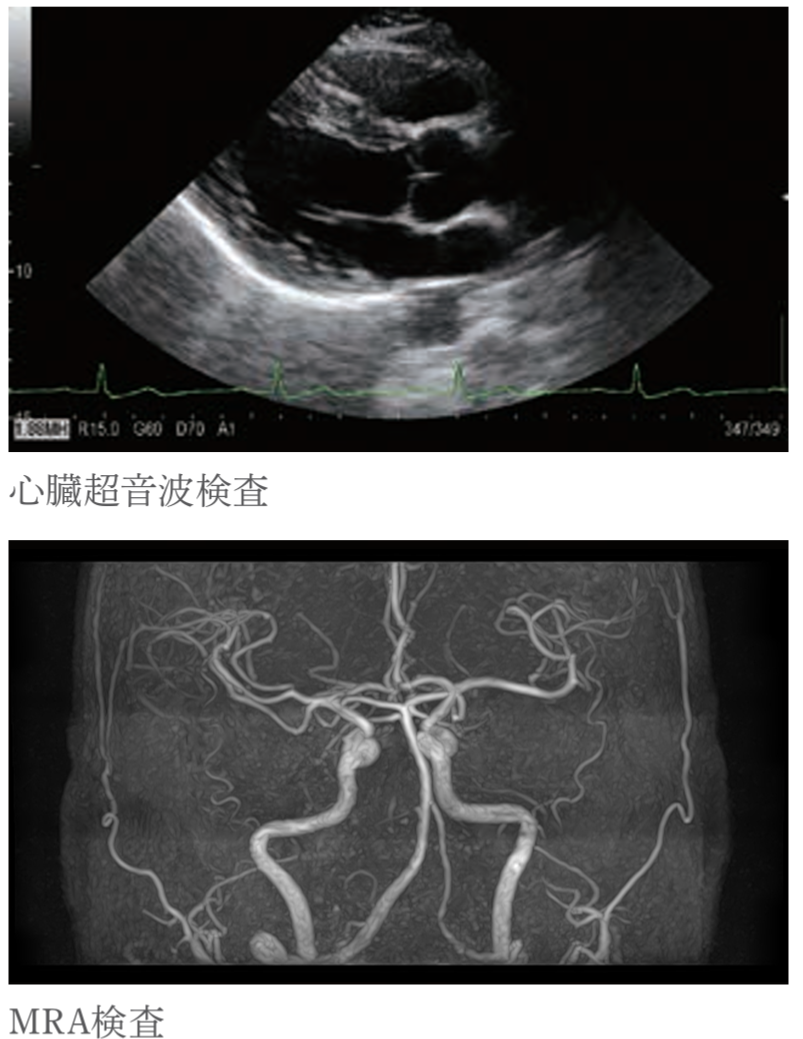

・頭頚部MRA検査

脳全体の血管を描き出し、脳動脈瘤などによるくも膜下出血や脳梗塞のリスクがないかを調べます。